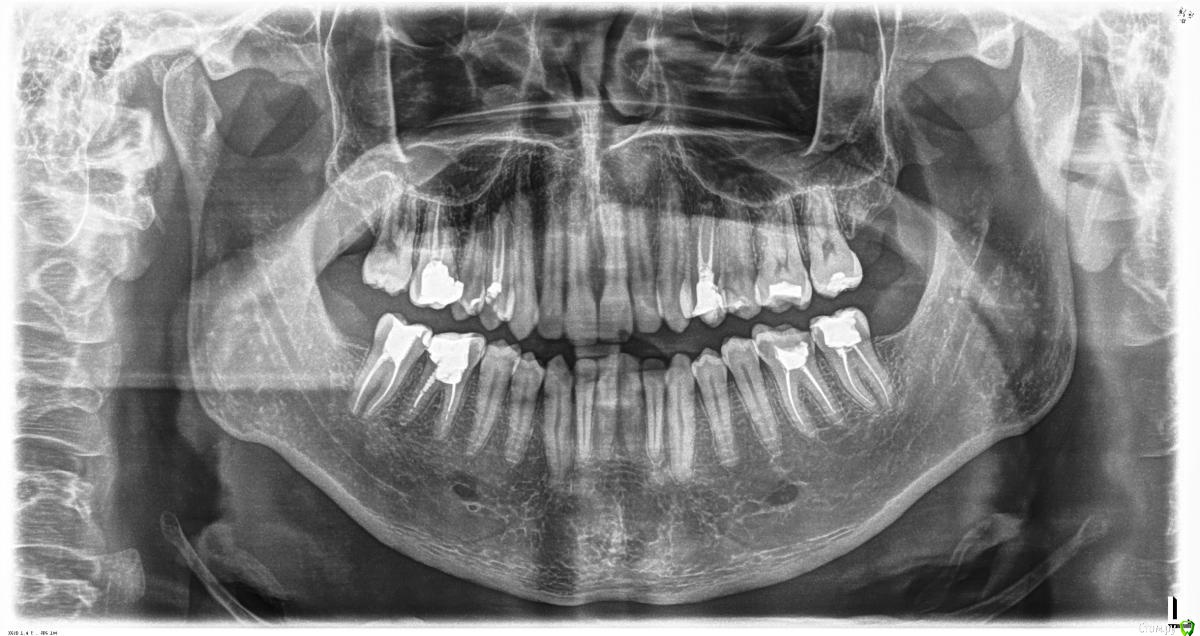

zdoroviy Опубликовано 29 октября, 2017 Поделиться Опубликовано 29 октября, 2017 Добрый день, 2 дня назад давно мертвый зуб начал реагировать на горячее, казалось ничего серьёзного, а ночью проснулся от сильнейшей боли в нижней 6 слева. К зубу было не притронуться. Всю ночь не спал, в субботу пошел к врачу, посмотрели снимок, сказали периодонтит, убрали старую пломбу, прочистили каналы, положили кальцивую пасту и закрыли временной пломбой. Пока отходило обезболивающее всё было нормально, ночью спал нормально, утром зуб поднывал, но не сильно, нпри накусывании чувствовалась боль. После обеда пошел на рынок за покупками и в один момент резко стрельнуло в зубе, боль словно нахлынула и прошла, тк случилось ещё несколько раз. Дома выпил обезболивающее и с ужасом жду ночи. У меня несколько вопросов: 1) Есть ли шанс спасти этот зуб не удаляя? 2) Что означает такая приходящая резкая боль? Это норма? и как долго она может продолжаться? 3) Нужно ли принимать антибиотики? Фото прилогаю Ссылка на комментарий